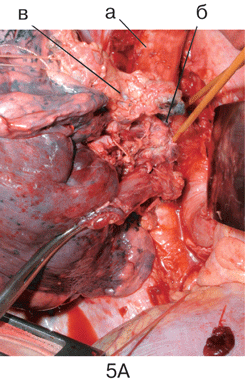

Именно поэтому прежде всего рассматривается вопрос о его использовании, и при отсутствии общеизвестных противопоказаний к операции, связанных с распространенностью опухоли или сниженными функциональными резервами, предпочтение отдается хирургическому методу. Онкологически адекватными являются операции в объеме пневмонэктомии и лобэктомии ;с систематической медиастинальной ипсилатеральной лимфодиссекцией (полноценное, выполняемое всегда удаление клетчатки с лимфатическими узлами переднего, заднего, верхнего и нижнего средостения на стороне поражения независимо от локализации опухоли в легком и размеров лимфоузлов), позволяющей повысить радикальность хирургического вмешательства, а также объективизирующей распространенность опухолевого процесса. В силу необходимости соблюдения радикализма эти операции могут дополняться резекцией соседних органов при их поражении (грудной стенки, диафрагмы, крупных сосудов верхней полой вены, легочной артерии, аорты и ее ветвей, предсердия, перикарда, бифуркации трахеи, пищевода и т.д.) (см. рис. 3–6 на цветной вклейке).

Рисунок 6. Вид послеоперационной раны после систематической медиастинальной билатеральной лимфодиссекции:

а- дуга аорты с отходящими ветвями; б – левая и правая плечеголовные вены, сливающиеся в ВПВ; в – трахея